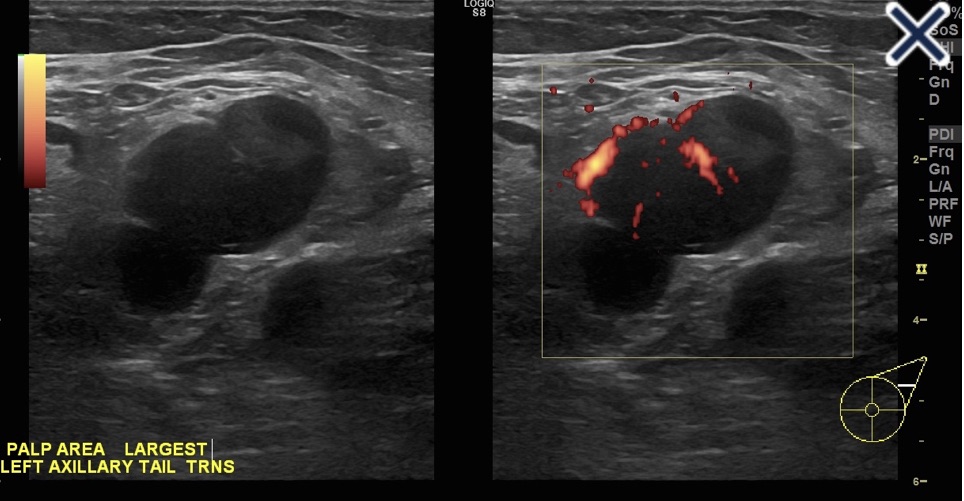

Lymph node completely replaced with metastatic carcinoma obliterating the fatty hilum. Doppler shows more than a single blood vessel supplying the node.

• When a lymph node is completely replaced with metastatic cancer:

• It will be rounded, hypoechoic, and the hilum will be completely obliterated (Image)